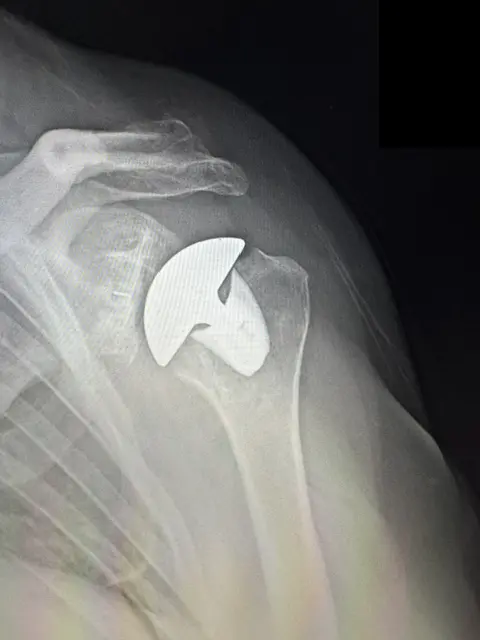

X-ray of a total shoulder replacement from Dr. Woodhead in Lincoln, NE

Total Shoulder Replacement

Total shoulder replacement is a surgical procedure that reconstructs the shoulder’s ball and socket by removing worn joint surfaces and restoring the joint’s anatomical structure.